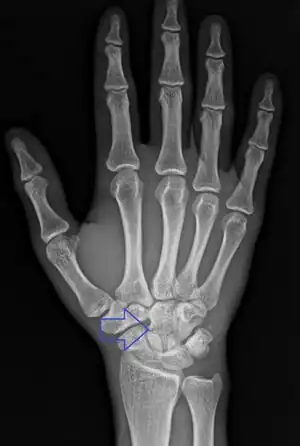

Typically they occur as a result of a fall on an outstretched hand or a direct blow to the back of the wrist.[1][2] Types include transverse body (most common), transverse pole, verticofrontal, and parasagittal.[1] Diagnosis is usually by X-rays.[1]

Diagnosis

Diagnosis is often by a posterior anterior wrist X-ray.[2]